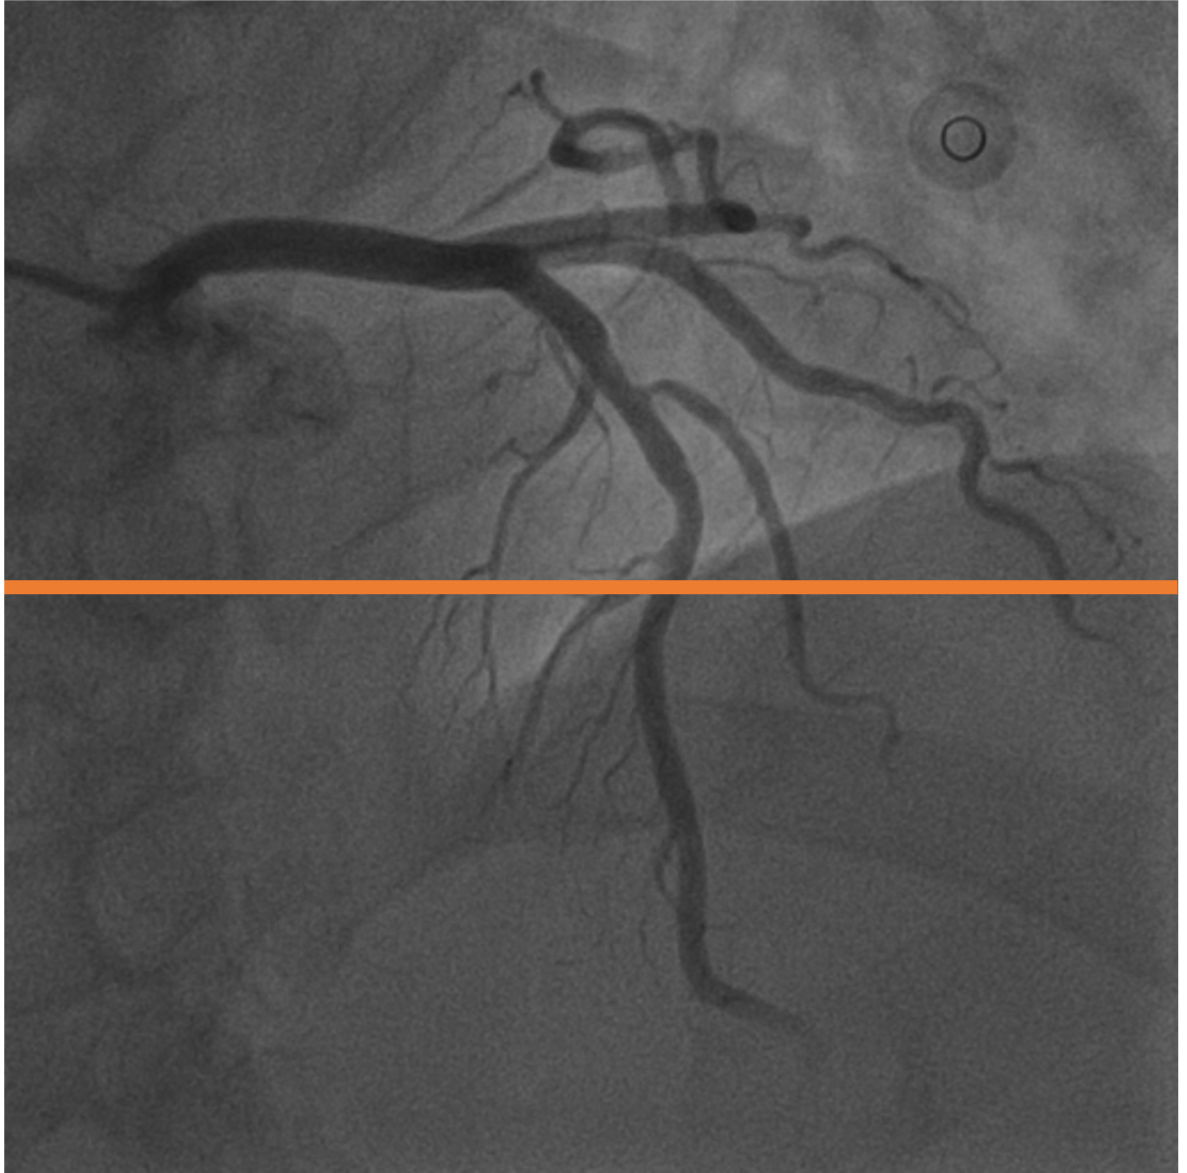

A.2 Temporal Coherency

Our method takes an entire X-ray video as input, thus producing segmentation results with better temporal coherency. Temporal coherency is essential for making medical diagnoses, especially when dealing with blood flow in vessels. Therefore, we conduct visual comparisons between our method and other compared methods by slicing horizontally or vertically and stacking the segmentation results. The results in Figure 12 show our method strikes a better balance between segmentation accuracy and temporal coherency. While other baseline methods either produce false segmentation results or do not maintain consistent prediction along the temporal dimension.